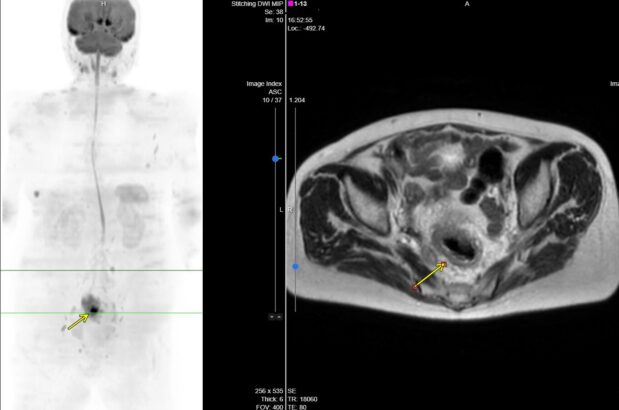

DWIBS検査で発見されたがんの一例

直腸がんの疑い